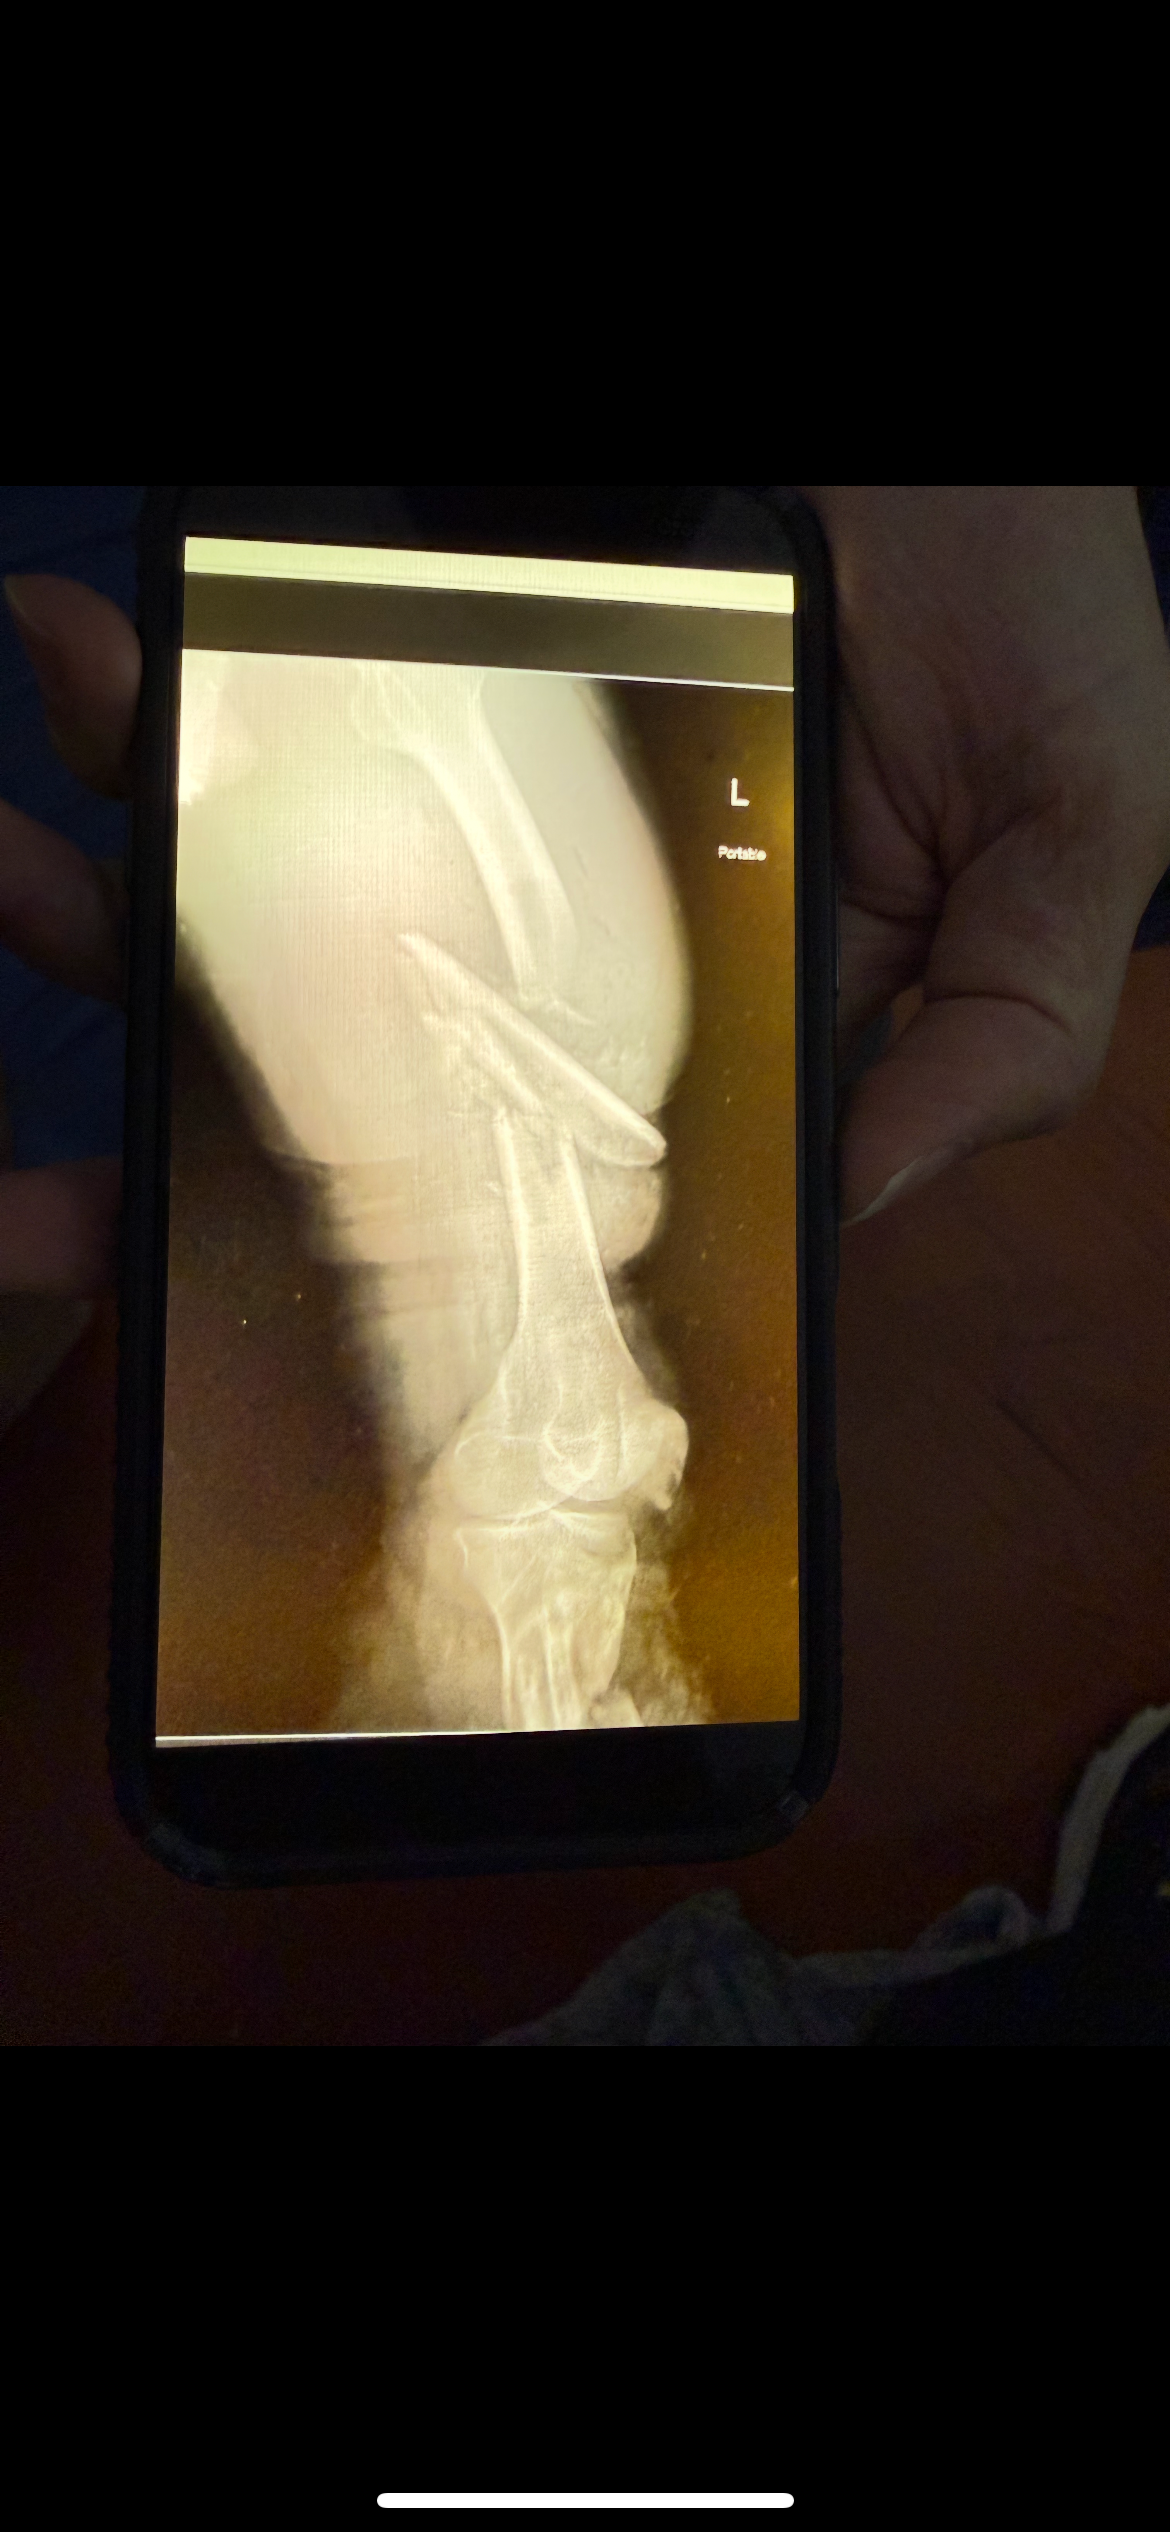

On October 5th, our dear friend Tony Day was in a devastating accident that changed his life in an instant. He suffered multiple severe injuries — including an above-the-knee amputation, collapsed lung, and fractures to his ribs, hips, and collarbone.